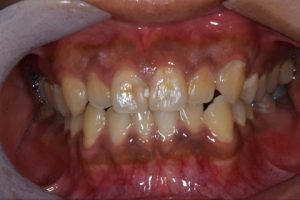

オフィスホワイトニング症例

治療前

治療後

主訴 着色除去・ホワイトニング

治療

内容

オフィスホワイトニング3回

方針

着色を除去しオフィスホワイトニングを行った

期間

1週間

費用 9,900円

担当

者所見

ホワイトニングを行ったことで着色も付きづらくなり、ホワイトニング歯磨き粉(スーパースマイル・アクセラレータ)の使用により白さのキープが出来ている